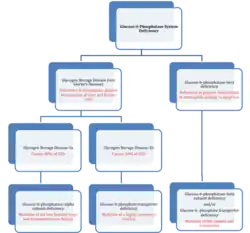

Mutations of the glucose 6-phosphatase system, to be specific the glucose 6-phosphatase-α subunit (glucose 6-phosphatase-α), glucose 6-transporter (G6PT), and glucose 6-phosphatase-β (glucose 6-phosphatase-β or G6PC3) subunits lead to deficiencies in the maintenance of interprandial glucose homeostasis and neutrophil function and homeostasis.[12][13] Mutations in both glucose 6-phosphatase-α and G6PT lead to glycogen storage disease type I (GSD 1, von Gierke's disease).[14] To be specific, mutations in the glucose-6-phosphatase-α lead to Glycogen Storage Disease Type-1a, which is characterized by accumulation of glycogen and fat in the liver and kidneys, resulting in hepatomegaly and renomegaly.[15] GSD-1a constitutes approximately 80% of GSD-1 cases that present clinically.[16] Absence of G6PT leads to GSD-1b (GSD-1b), which is characterized by the lack of a G6PT and represents 20% of the cases that present clinically.[16][17]

The specific cause of the GSD-1a stems from nonsense mutations, insertions/deletions with or without a shift in the reading frame, or splice site mutations that occur at the genetic level.[7] The missense mutations affect the two large luminal loops and transmembrane helices of glucose 6-phosphatase-α, abolishing or greatly reducing activity of the enzyme.[7] The specific cause of GSD-1b stems from "severe" mutations such as splice site mutations, frame-shifting mutations, and substitutions of a highly conserved residue that completely destroyed G6PT activity.[7] These mutations lead to the prevalence of GSD-1 by preventing the transport of glucose-6-phosphate (G6P) into the luminal portion of the ER and also inhibiting the conversion of G6P into glucose to be used by the cell.

The third type of glucose 6-phosphatase deficiency, glucose 6-phosphatase-β deficiency, is characterized by a congenital neutropenia syndrome in which neutrophils exhibit enhanced endoplasmic reticulum (ER) stress, increased apoptosis, impaired energy homeostasis, and impaired functionality.[18] It can also lead to cardiac and urogenital malformations.[19] This third class of deficiency is also affected by a G6PT deficiency as glucose-6-phosphatase-β also lies within the ER lumen and thus can lead to similar symptoms of glucose-6-phosphatase-β deficiency be associated with GSD-1b.[17] Furthermore, recent studies have elucidated this area of similarity between both deficiencies and have shown that aberrant glycosylation occurs in both deficiencies.[20] The neutrophil glycosylation has a profound effect on neutrophil activity and thus may also be classified as a congenital glycosylation disorder as well.[20]

The major function of glucose 6-phosphatase-β has been determined to provide recycled glucose to the cytoplasm of neutrophils in order maintain normal function. Disruption of the glucose to G6P ratio due to significant decrease intracellular glucose levels cause significant disruption of glycolysis and HMS.[13] Unless countered by uptake of extracellular glucose this deficiency leads to neutrophil dysfunction.[13]